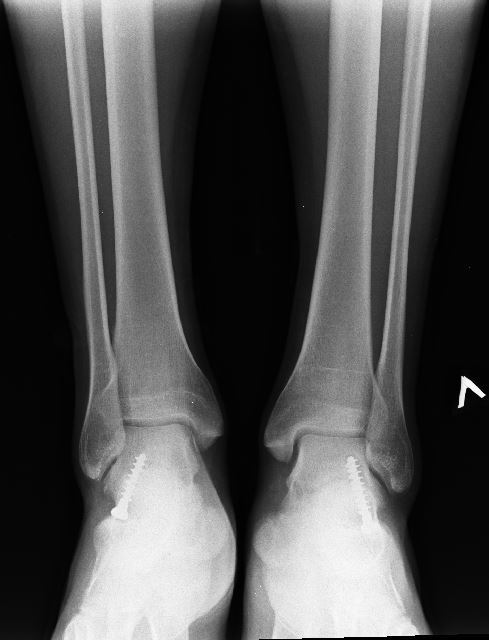

Напомню: это операция по коррекции плоскостопия с помощью "винтов" - у меня после операции 3 степень плоскостопия стала 2-й. Подробнее можете почитать в предыдущем посте.

Винты всё ещё в стопах, решено пока воздержаться от их удаления.

Прикладываю фото стелек и последние актуальные снимки.